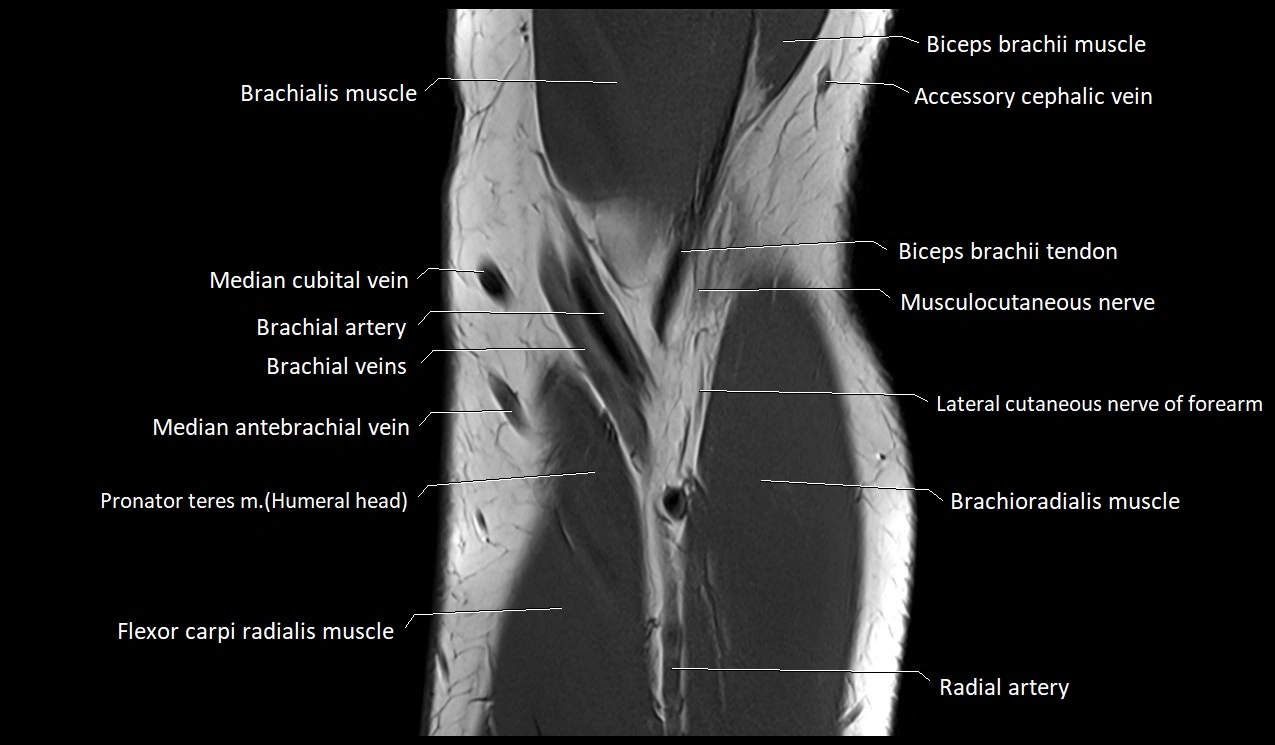

MRI image

image